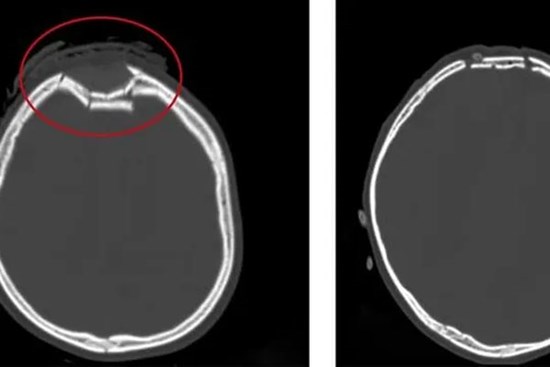

Bánh xe cuốn tà áo dài, nữ sinh bị đập đầu xuống đường nứt hộp sọ

Trên đường đến trường, nữ sinh 15 tuổi ở Tây Ninh bất ngờ ngã đập đầu xuống đường khi tà áo dài bị cuốn vào bánh sau xe đạp điện. Tai nạn tưởng chừng đơn giản đã khiến em rơi vào tình trạng chấn thương sọ não nguy kịch tính mạng.